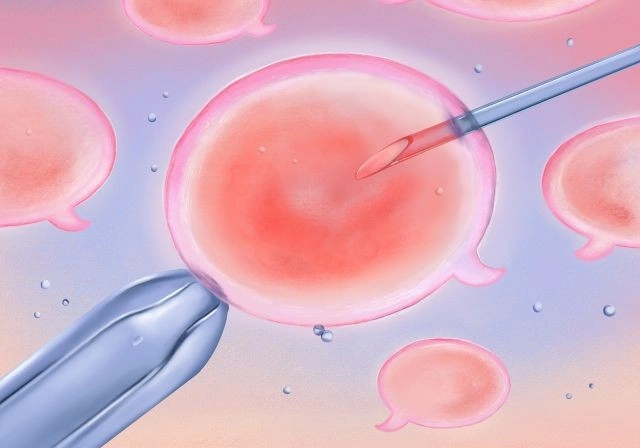

الحقن المجهري هو أحد تقنيات الإخصاب المساعد، ويتم فيه:

تنشيط المبايض لإنتاج عدد مناسب من البويضات

سحب البويضات في إجراء بسيط

حقن حيوان منوي واحد مباشرة داخل كل بويضة (ICSI)

متابعة نمو الأجنة داخل المعمل

نقل جنين أو أكثر إلى الرحم